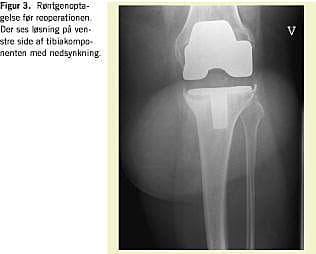

Indførelsen af antibiotika- og tromboseprofylakse ved ortopædkirurgi har mindsket hyppigheden hos overvægtige af alvorlige perioperative komplikationer til alloplastikbehandling. Langtidsresultaterne af alloplastikbehandling af disse patienter er dog generelt ringere end hos normalvægtige (Figur 1, Figur 2 , Figur 3 og Figur 4 ). Englund konstaterede hos meniskektomerede patienter med BMI > 30 kg/m2 en større hyppighed af knæ-OA end hos normalvægtige (BMI < 25 kg/m2 ) [16].